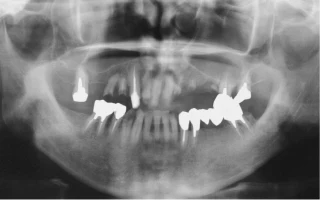

1日で抜歯・インプラント埋入・仮歯装着まで!ワンデイインプラント®

歯周病やむし歯でほとんどの歯を抜かなくていけないと診断されたけれど、どうしても入れ歯を使用することは許容できない。そんな方には、抜歯と同時にインプラント埋入をおこない、さらに同日に固定性の仮歯まで装着できるワンデイインプラント®がオススメです。

01.概要

重度の歯周病や多数のむし歯のよって、残念ながらほとんど全ての歯を抜歯しなければいけないと診断されたしまった場合、どうすれば良いのでしょうか?通常であれば、あらかじめ入れ歯を作っておいて、抜歯した当日に入れ歯を装着するのが通常の治療法です。しかし、抜歯した直後の入れ歯の適合はあまり良好ではなく、入れ歯が不安定だったり、しっかりものが噛めなかったりすることがよくあります。

入れ歯や歯がない状態で生活することが難しい、あるいはどうしても許容できない方に対して、即日で抜歯とインプラント埋入と仮歯の装着が可能となる画期的な治療法が、このワンデイインプラント®です。

ワンデイインプラント®とは、当院理事長のインプラントの師の一人でもある、東京銀座歯科院長の中平宏先生が考案した方法で、抜歯した即日に4〜6本のインプラントを埋入し、その日に仮歯まで装着する画期的な治療法です。